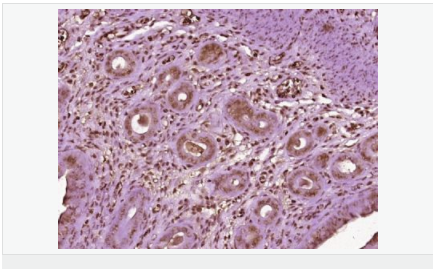

| 英文名稱(chēng) | Progesterone Receptor |

| 中文名稱(chēng) | 孕激素受體抗體 |

| 別 名 | NR3C3; Nuclear receptor subfamily 3 group C member 3; PGR; PR; PRA; PRB; Progesterone receptor; Progestin receptor form A; Progestin receptor form B; PRGR_HUMAN; Progestin receptor form A; Progestin receptor form B. |

| 研究領(lǐng)域 | 腫瘤 免疫學(xué) 信號轉導 生長(cháng)因子和激素 腫瘤細胞生物標志物 |

| 產(chǎn)品應用 | WB=1:500-2000 IHC-P=1:100-500 IHC-F=1:100-500 Flow-Cyt=1ug/Test ICC=1:100-500 IF=1:100-500 (石蠟切片需做抗原修復) not yet tested in other applications. optimal dilutions/concentrations should be determined by the end user. |

| 細胞定位 | 細胞核 細胞漿 |

| 產(chǎn)品介紹 | Estrogen and progesterone receptor are members of a family of transcription factors that are regulated by the binding of their cognate ligands. The interaction of hormone-bound estrogen receptors with estrogen responsive elements(EREs) alters transcription of ERE-containing genes. The carboxy terminal region of the estrgen receptor contains the ligand binding domain, the amino terminus serves as the transactivation domain, and the DNA binding domain is centrally located. Two forms of estrogen receptor have been identified, ER alpha and ER beta. ER alpha and ER beta have been shown to be differentially activated by various ligands. The biological response to progesterone is mediated by two distinct forms of the human progesterone receptor (hPR-Aand hPR-B), which arise from alternative splicing. In most cells, hPR-B functions as a transcriptional activator of progesterone-responsive gene, whereas hPR-A function as a transcriptional inhibitor of all steroid hormone receptors. Function: The steroid hormones and their receptors are involved in the regulation of eukaryotic gene expression and affect cellular proliferation and differentiation in target tissues. Progesterone receptor isoform B (PRB) is involved activation of c-SRC/MAPK signaling on hormone stimulation. Isoform A is inactive in stimulating c-Src/MAPK signaling on hormone stimulation. Subunit: Interacts with SMARD1 and UNC45A. Interacts with CUEDC2; the interaction promotes ubiquitination, decreases sumoylation, and repesses transcriptional activity. Interacts with PIAS3; the interaction promotes sumoylation of PR in a hormone-dependent manner, inhibits DNA-binding, and alters nuclear export. Interacts with SP1; the interaction requires ligand-induced phosphorylation on Ser-345 by ERK1/2 MAPK. Interacts with PRMT2. Subcellular Location: Nucleus. Cytoplasm. Note=Nucleoplasmic shuttling is both homone- and cell cycle-dependent. On hormone stimulation, retained in the cytoplasm in the G(1) and G(2)/M phases. Isoform A: Nucleus. Cytoplasm. Note=Mainly nuclear. Post-translational modifications: Phosphorylated on multiple serine sites. Several of these sites are hormone-dependent. Phosphorylation on Ser-294 occurs preferentially on isoform B, is highly hormone-dependent and modulates ubiquitination and sumoylation on Lys-388. Phosphorylation on Ser-102 and Ser-345 also requires induction by hormone. Basal phosphorylation on Ser-81, Ser-162, Ser-190 and Ser-400 is increased in response to progesterone and can be phosphorylated in vitro by the CDK2-A1 complex. Increased levels of phosphorylation on Ser-400 also in the presence of EGF, heregulin, IGF, PMA and FBS. Phosphorylation at this site by CDK2 is ligand-independent, and increases nuclear translocation and transcriptional activity. Phosphorylation at Ser-162 and Ser-294, but not at Ser-190, is impaired during the G(2)/M phase of the cell cycle. Phosphorylation on Ser-345 by ERK1/2 MAPK is required for interaction with SP1. Sumoylation is hormone-dependent and represses transcriptional activity. Sumoylation on all three sites is enhanced by PIAS3. Desumoylated by SENP1. Sumoylation on Lys-388, the main site of sumoylation, is repressed by ubiquitination on the same site, and modulated by phosphorylation at Ser-294. Similarity: Belongs to the nuclear hormone receptor family. NR3 subfamily. Contains 1 nuclear receptor DNA-binding domain. SWISS: P06401 Gene ID: 5241 Database links: Entrez Gene: 5241 Human Entrez Gene: 18667 Mouse Entrez Gene: 100009094 Rabbit Omim: 607311 Human SwissProt: P06401 Human SwissProt: Q00175 Mouse SwissProt: P06186 Rabbit Unigene: 2905 Human Unigene: 32405 Human Unigene: 742403 Human Unigene: 12798 Mouse Unigene: 437703 Mouse Unigene: 1947 Rabbit Unigene: 10303 Rat Important Note: This product as supplied is intended for research use only, not for use in human, therapeutic or diagnostic applications. |